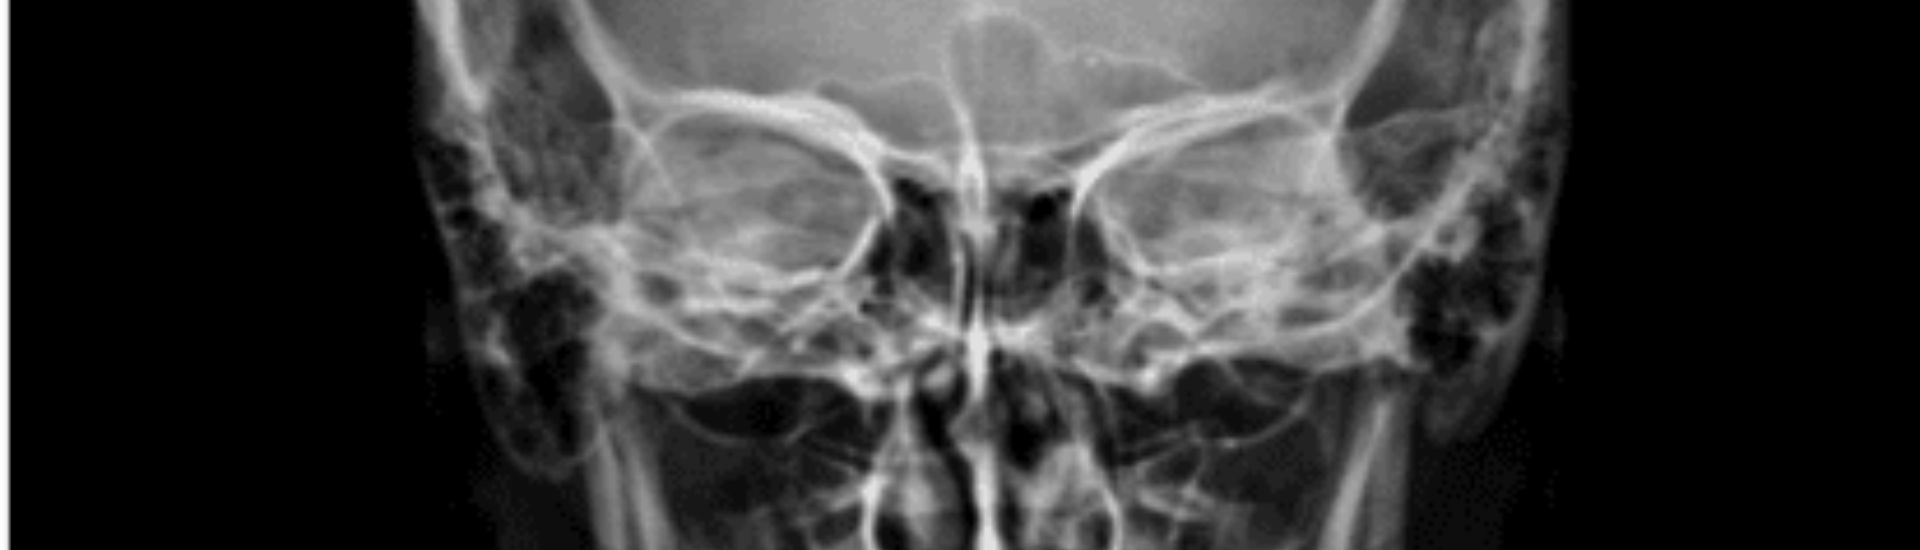

L’RX Orbite è un esame radiologico non invasivo che permette di acquisire immagini dettagliate delle orbite oculari. Il paziente viene posizionato davanti a una macchina a raggi X e, grazie a questa tecnologia, si ottiene una visualizzazione chiara delle strutture interne. Le immagini mostrano non solo le ossa, ma anche i muscoli oculari e i tessuti molli circostanti, consentendo ai medici del Poliambulatorio S-Medical Group di Sora di valutare con precisione ogni potenziale anomalia.

Durante l’esame di RX Orbite, il paziente viene esposto a una dose molto bassa di radiazioni ionizzanti. Le radiazioni attraversano i tessuti e le ossa dell’orbita, generando un’immagine radiografica precisa che permette di distinguere le diverse strutture. I tessuti più densi, come le ossa, appaiono più chiari, mentre i tessuti molli risultano più scuri. Questo contrasto consente ai medici di individuare eventuali anomalie con grande accuratezza.

L’RX Orbite permette di osservare le ossa che costituiscono le pareti dell’orbita (mediale, laterale, superiore e inferiore), la posizione del bulbo oculare, i muscoli oculari, i nervi ottici e le strutture vascolari. Queste informazioni dettagliate sono fondamentali per identificare fratture, alterazioni strutturali o anomalie nella posizione degli occhi.